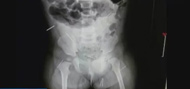

濟南:11個月女嬰體內(nèi)插入16根鋼針

濟南:11個月女嬰體內(nèi)插入16根鋼針 2014-10-23 09:07:33

鋼針.jpg

濟南:11個月女嬰...